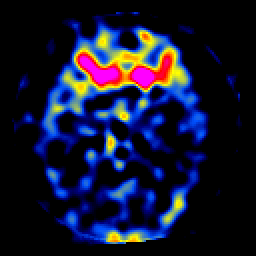

SPECT TL Study #7 -- Slice #21